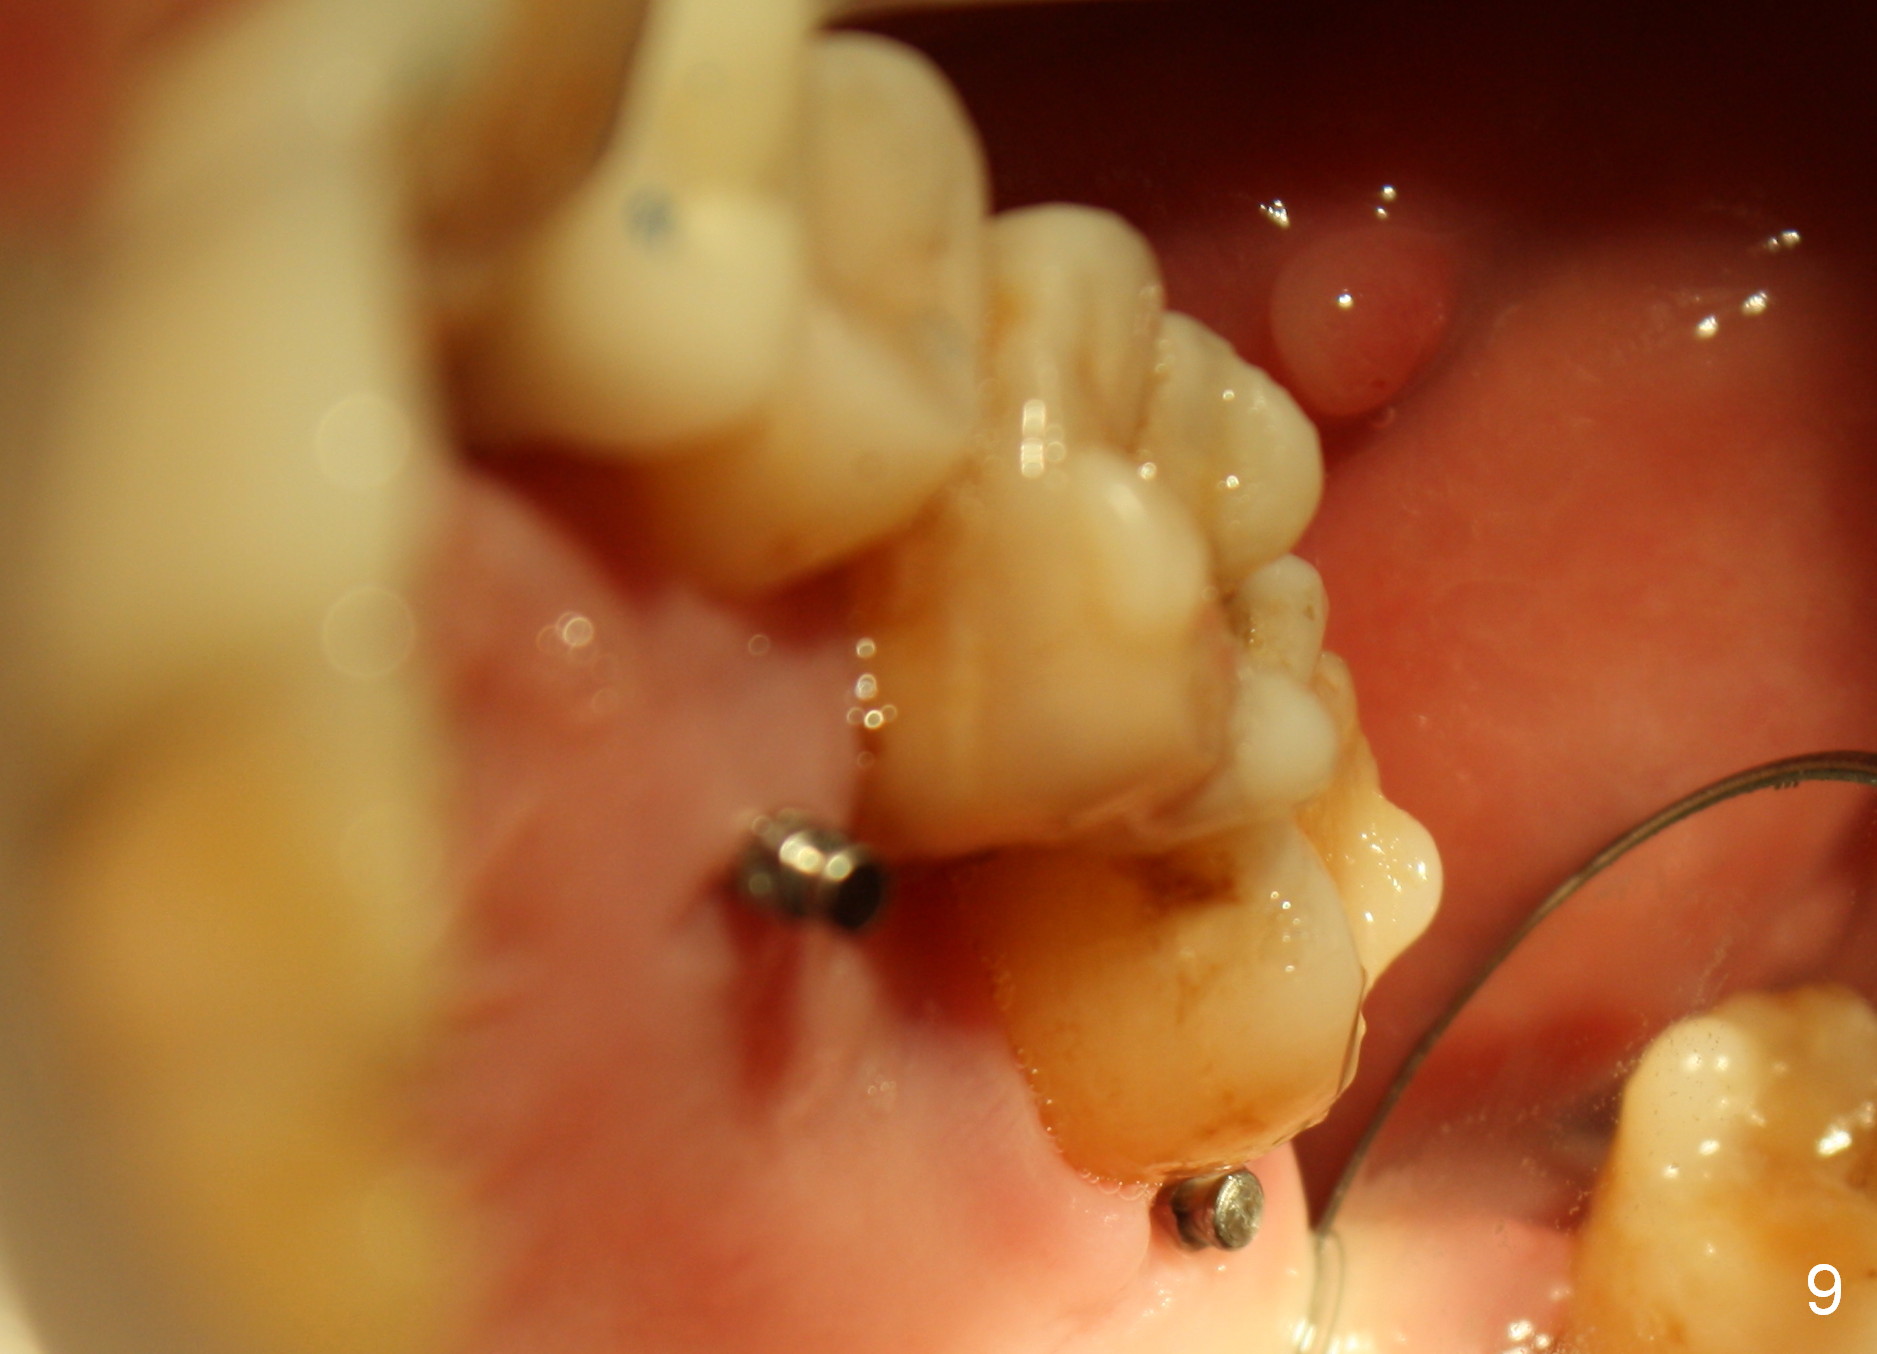

A 41-year-old man has chronic periodontits with bruxism. The teeth #14 and 15 are supraerupted (Fig.1 arrows) with furcal lesion (Fig.2 (CT) *). These 2 molars have guarded to poor prognosis. Due to insurance benefit limitation, we plan to save them temporarily with periodontal surgery so that bone loss would not get worse when the teeth are being intruded. After opposing implant placement (Fig.3), flaps are raised to remove calculus and granulation tissue (Fig.4, no bone graft). Twenty days later, three mini-implants are placed (Fig.5,6). The implant distopalatal to #15 is loose nearly 2 months postop (Fig.7 *) and retightened. The following month the same implant is placed higher for stability (Fig.8). The Intrusion takes <5.5 months (Fig.9,10).